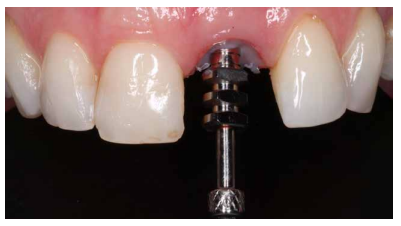

Se obtuvo estabilidad primaria, logrando anclaje en el hueso residual palatino a un torque de inserción de 35 N/cm2 . Posteriormente, se procedió a la colocación de un pilar temporal protésico.

Fase protésica provisional

Antes del comienzo de la rehabilitación provisional atornillada sobre el IOI, se comprobó la correcta disposición del pilar en cuanto a la prótesis provisional. Se llevó a cabo el rebase del pilar con el provisional a través del uso de composite fluido (Figuras 8 y 9).